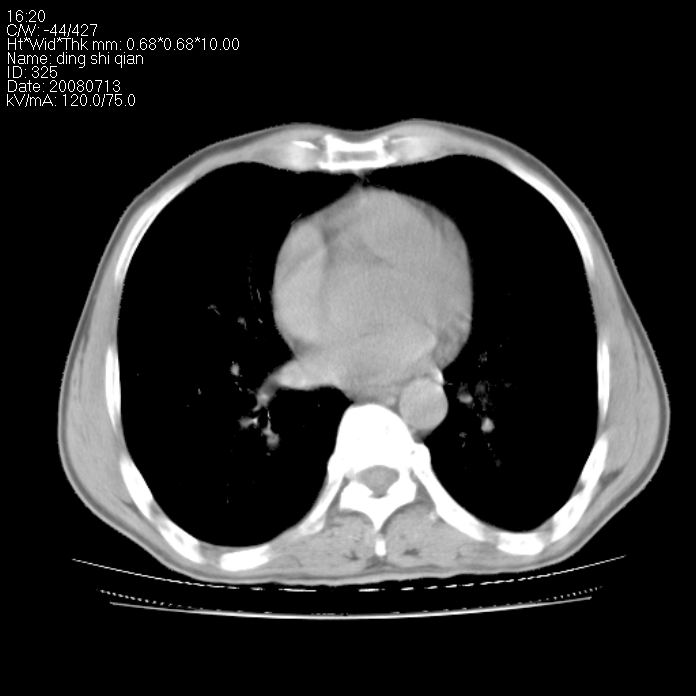

标题: CT14654:男 50岁 近来胸痛 [打印本页]

标题: CT14654:男 50岁 近来胸痛

右侧上肺块状软组织影,浅分叶,边缘毛刺证,与胸膜粘连,考虑:周围性肺癌

右侧上肺块状软组织影,浅分叶,边缘毛刺证,与胸膜粘连,考虑:周围性肺癌!支持!

以下是引用晓杰在2008-7-16 22:00:00的发言:[br]右侧上肺块状软组织影,浅分叶,边缘毛刺证,与胸膜粘连,考虑:周围性肺癌